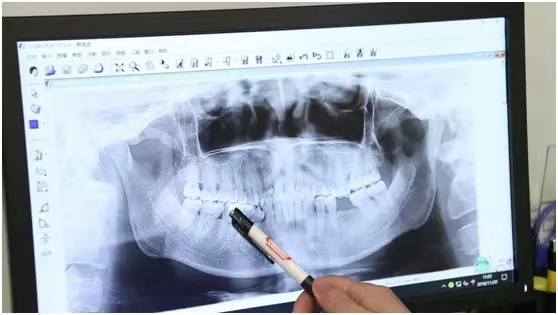

五、種植牙到底是如何“種”的?

種植牙手術(shù)的流程:種植前檢查→取模型→進行骨質(zhì)、骨量的分析→設定方案→一期手術(shù)→二期手術(shù)→戴牙冠→術(shù)后護理